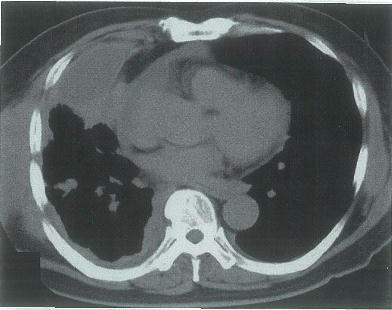

65歳の男性。右前胸部の疼痛を主訴に来院した。2か月前から乾性咳嗽と労作時の呼吸困難とが出現し,徐々に増悪した。16歳から60歳まで自動車整備工をしていた。喫煙は20本/日を45年間。意識は清明。身長 168cm,体重 54kg。体温 37.0℃。脈拍 76/分,整。血圧 130/90mmHg。胸部右側の呼吸音の減弱を認める。血液所見:赤血球 429万,Hb 14.6g/dl,Ht 45%,白血球 4100,血小板 20万。血液生化学所見:総蛋白 7.5g/dl,アルブミン 3.5g/dl,AST 22IU/l,ALT 9IU/l,LDH 128IU/l(基準 176~353)。CRP 0.2mg/dl。穿刺排液した胸水は黄色混濁で,比重 1.019。蛋白 5.2g/dl,LDH 151IU/l,アデノシンデアミナーゼ 45.0IU/l(基準 50以下),ヒアルロン酸高値。一般細菌および抗酸菌培養は陰性で,結核菌のPCR検査も陰性であった。胸部単純CTを別に示す。確定診断のため,胸腔鏡下で壁側胸膜上の結節を生検した。生検組織のH-E染色標本とカルレチニン免疫組織染色標本とを別に示す。CEAによる免疫組織染色は陰性であった。

71歳の男性。呼吸困難を主訴に来院した。20歳から40年間,ビル建設の仕事に従事した。喫煙 20本/日を30年間。胸水中のヒアルロン酸は92300ng/mlと著明な増加を示す。胸部エックス線写真と胸腹部造影CTとを別に示す。